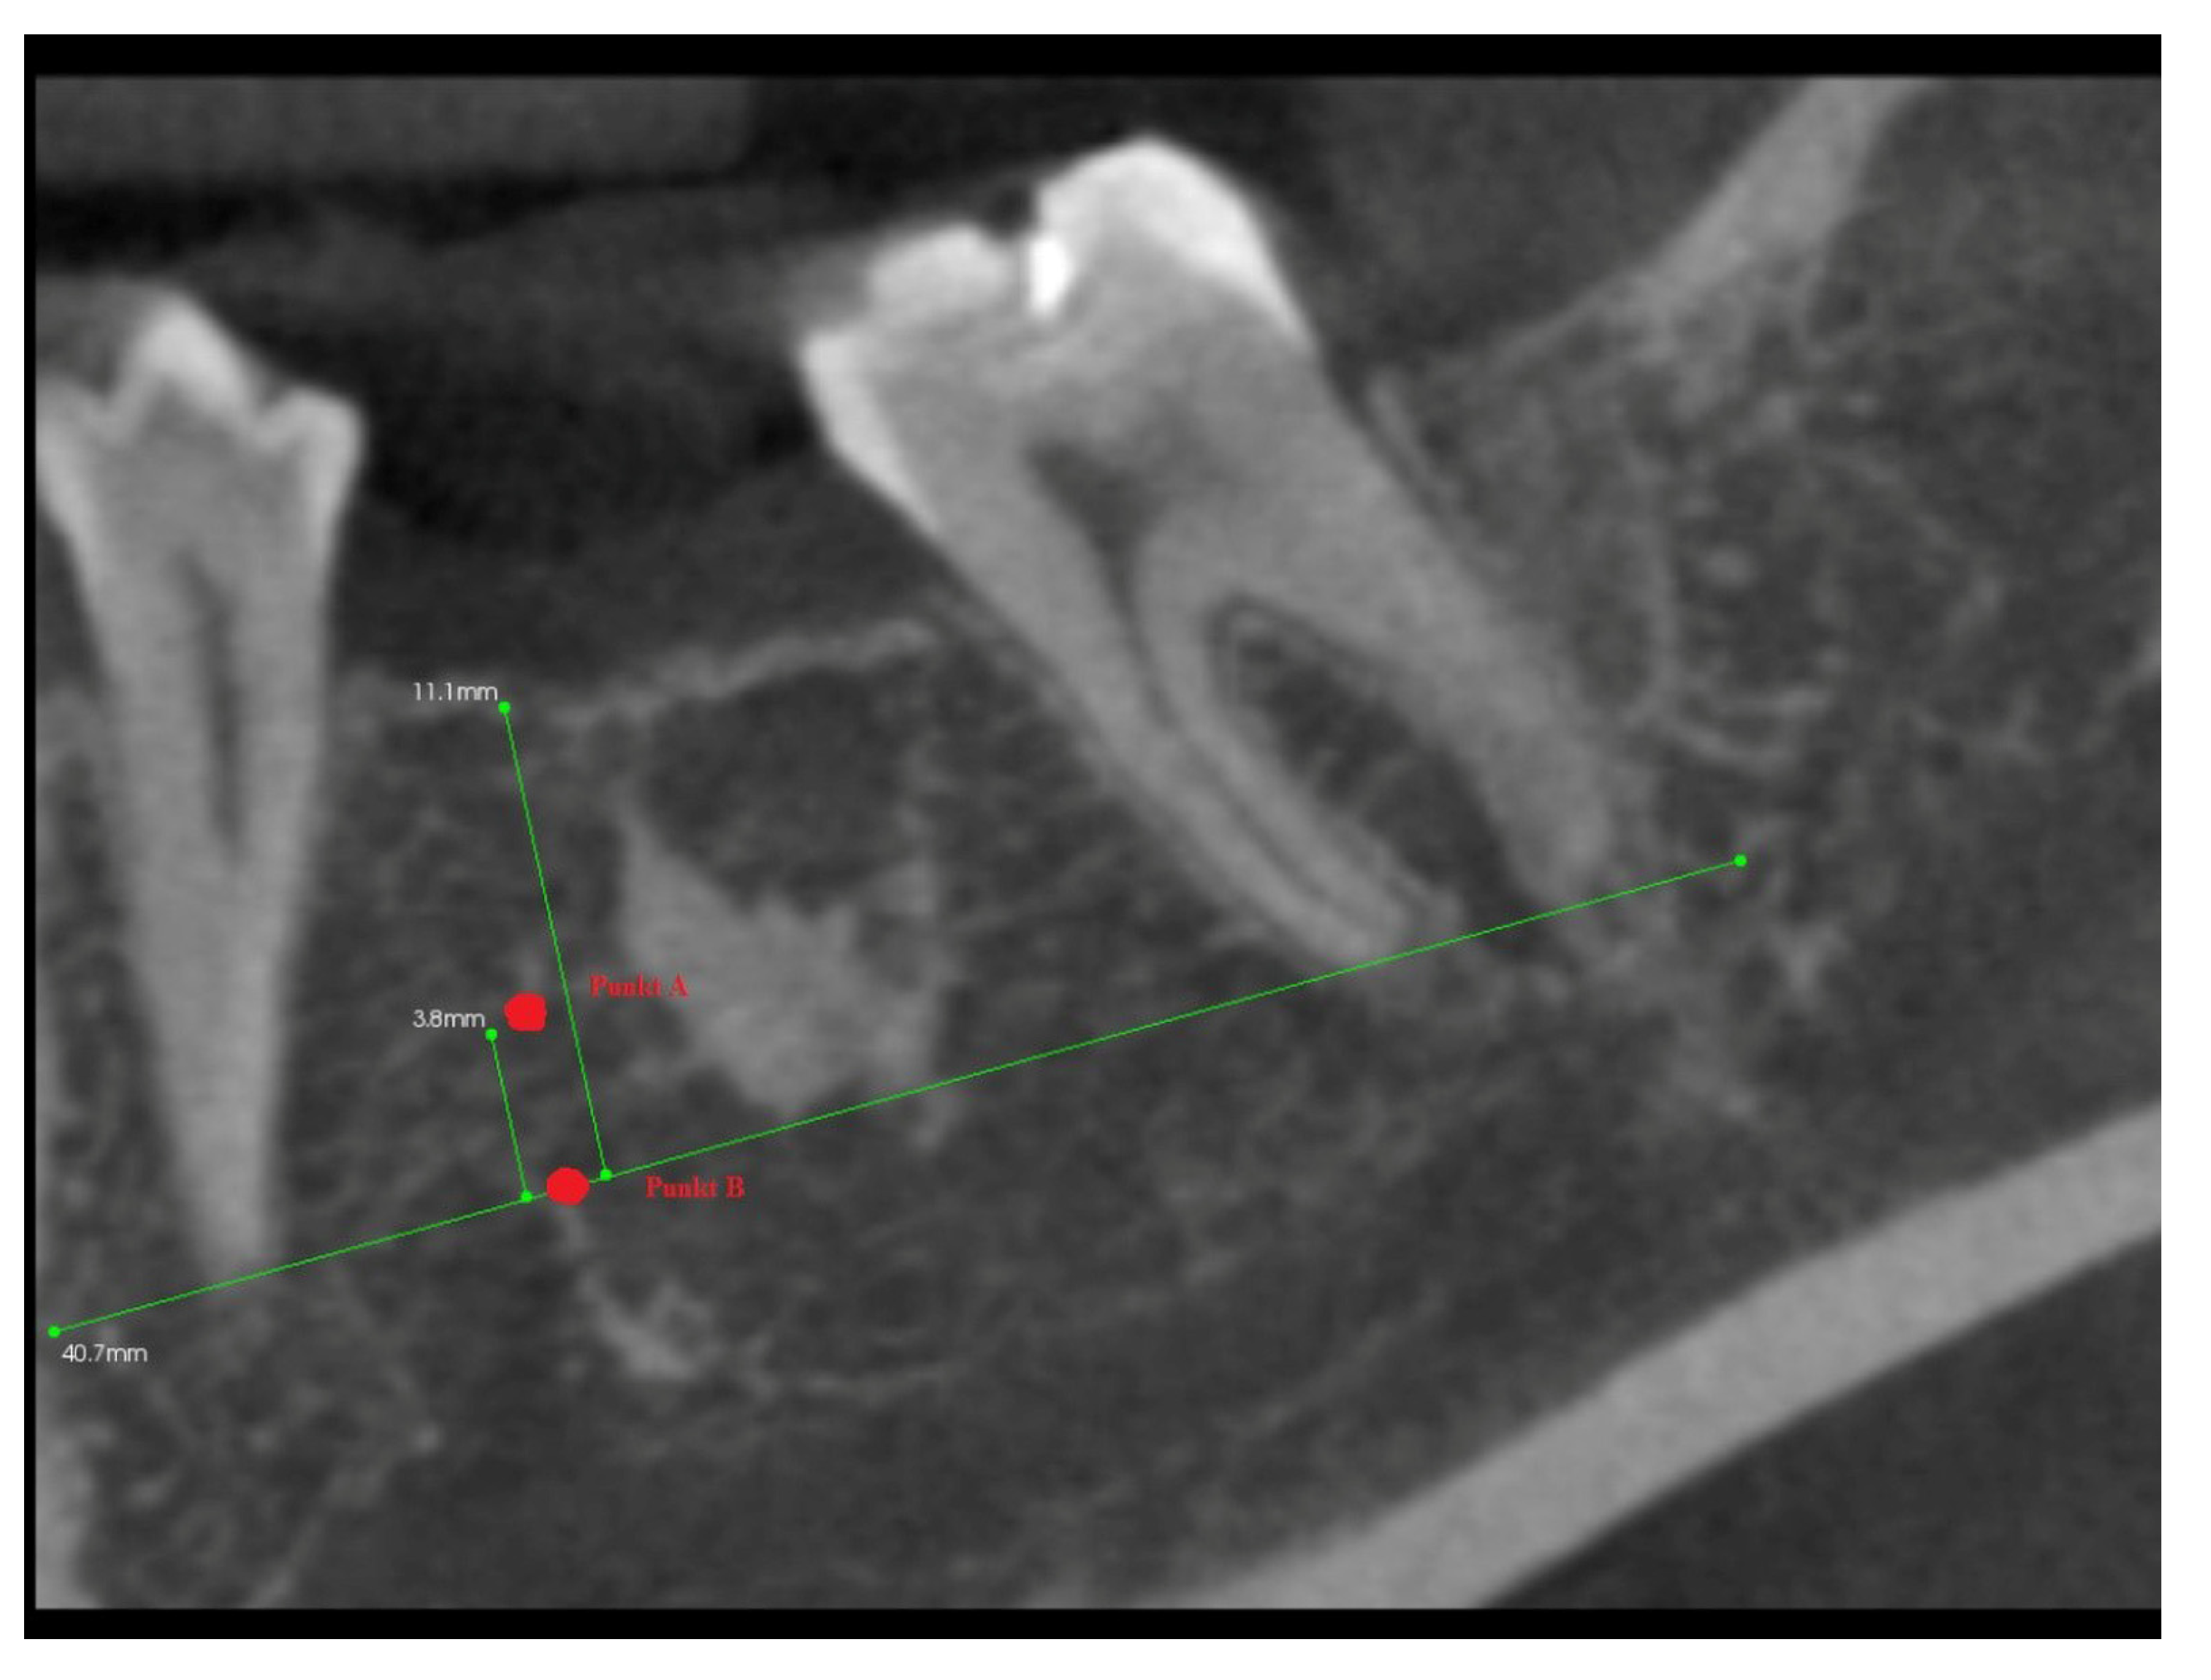

- The A line drawn through the apexes of the teeth adjacent to the post-extraction socket;

- The IC line drawn through the top of the buccal cusps of the teeth adjacent to the pos-extraction socket;

- The midline of the post-extraction socket (alveolus).

- Point (A)

- 1/3 of the distance between the A line and the IC line following the midline;

- Point (B)

- At the intersection of the midline and the A line.

3.2. The Results of Mean Values of the Alveolar Process Width and Height Measurements Performed after Tooth Extraction within the Space of 6 Months for Two Different Alveoli in the Same Patient

3.4. The Results of Mean Measurements of Height and Width of the Alveolar Processes of Two Extraction Sites (with and without PRF) in the Same Patient after 6 Months from Tooth Extraction Based on the Analysis of Volumetric Tomography

Author Contributions